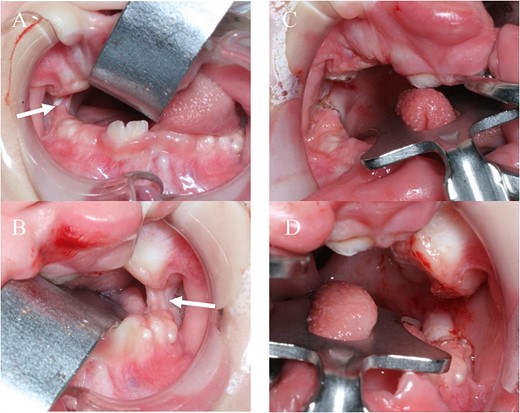

A female infant diagnosed with bilateral cleft lip on prenatal ultrasound was born weighing 3032 g at 40 weeks of gestation. She was transferred to the neonatal intensive care unit and intubated for respiratory distress. Postnatal IRF6 mutation analysis demonstrated NM_006147:exon4:c.C250G:p.R84G, confirming the diagnosis of PPS. Physical examination showed bilateral web of the bottom of the knees and bilateral syndactyly, BCLP, fistulas of the lower lip, and bilateral congenital cords between the maxilla and mandible causing syngnathia with trismus (maximum mouth opening: 5 mm) (Fig. 1A, B). Trismus improved by 30 mm after cutting the cords (maximum mouth opening: 35 mm), allowing the patient to achieve oral intake (Fig. 1C, D). Moreover, the oral mucosa appeared to be folded on the hard palate, and the short soft palate was classified as Randall type III in which the distal tips of one or both uvulae do not even reach as far as the adenoids (Fig. 2A) [3].

A, B: before release surgery, syngnathia is seen on both sides (white arrow); C, D: after surgery, syngnathia is released on both sides.